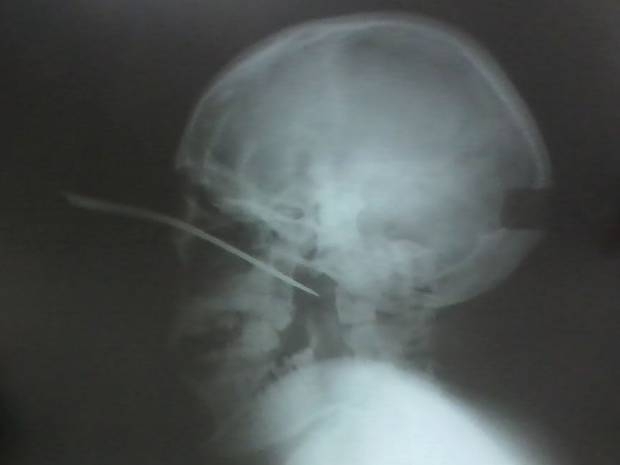

Jovem de 17 anos é ferido e fica com uma faca na cabeça

Um jovem de 17 anos foi ferido com uma faca após uma briga durante uma festa em comemoração ao Dia do Índio no município de Jacareacanga, no sudoeste do Pará. Ele foi atacado na cabeça com o objeto cortante, que quebrou na mão do agressor e ficou cravada no olho esquerdo do adolescente.